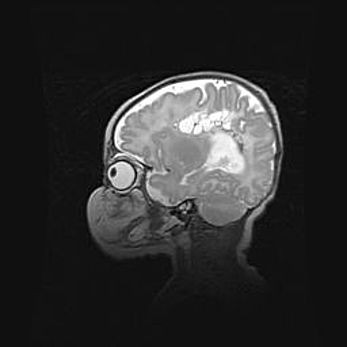

Сообщающаяся гидроцефалия. Кистозная энцефаломаляция головного мозга.

Возраст: 3 месяца 4 дня

Вес: 3100 г

Пол: женский

Окружность головы: 34 см

Срок гестации: 31 неделя

Кистозная энцефаломаляция головного мозга - одна из форм поражения головного мозга в детском возрасте. Характеризуется возникновением множественных и распространённых кист в коре, белом веществе и подкорковых образованиях головного мозга у плодов, новорождённых и детей раннего возраста. Развитие кистозной энцефаломаляции связано с внутриутробной асфиксией и гипотонией, родовой травмой, тромбозом синусов, пороками развития сосудов, инфекциями, сепсисом и другими причинами. Наиболее значимые инфекционные агенты: вирусы простого герпеса, цитомегалии, краснухи, токсоплазмы, энтеробактерии, золотистый стафилококк и другие.